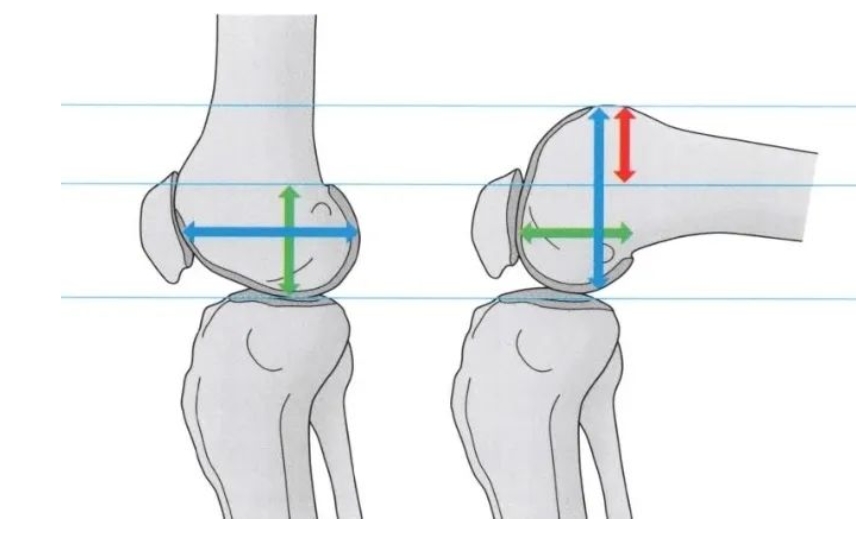

术后康复:膝关节屈曲90°活动受限的原因?